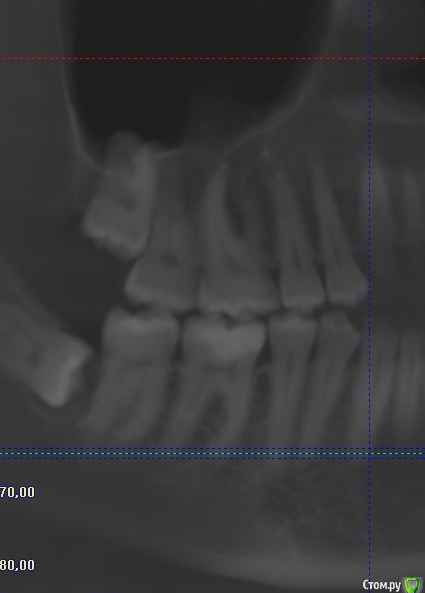

Aline7 Опубликовано 6 апреля, 2015 Поделиться Опубликовано 6 апреля, 2015 Добрый вечер. Проблема такая, несколько месяцев периодами побаливает в районе шестого, седьмого зуба сверху.Терапевт говорит с ними все в порядке. Возможно ли это из-за восьмого зуба, который упирается в седьмой?Если его удалить, может ли возникнуть перфорация в гайморовой пазухе? Ссылка на комментарий

DR.P Опубликовано 6 апреля, 2015 Поделиться Опубликовано 6 апреля, 2015 Да, конечно 8 может быть причиной тянущих болей в области 6 и 7 зубов. При удалении 8 безусловно может образоваться перфорация, удалять нужно деликатно, после удаления лучше ушить лунку. Даже если перфорация случится при грамотных действиях врача стоматолога можно избежать осложнений. 1 Ссылка на комментарий

red_butler Опубликовано 7 апреля, 2015 Поделиться Опубликовано 7 апреля, 2015 Я бы еще внимательно посмотрел 4.6 1 Ссылка на комментарий

Aline7 Опубликовано 7 апреля, 2015 Автор Поделиться Опубликовано 7 апреля, 2015 Спасибо большое за ответы. Да, на 4.6 поставили в свое время большую пломбу, недавно поменяли, но тоже иногда ноет немного. Видимо придется снова обращаться к врачу с этой проблемой. Ссылка на комментарий

red_butler Опубликовано 7 апреля, 2015 Поделиться Опубликовано 7 апреля, 2015 Но зубы мудрости лучше удалить Ссылка на комментарий